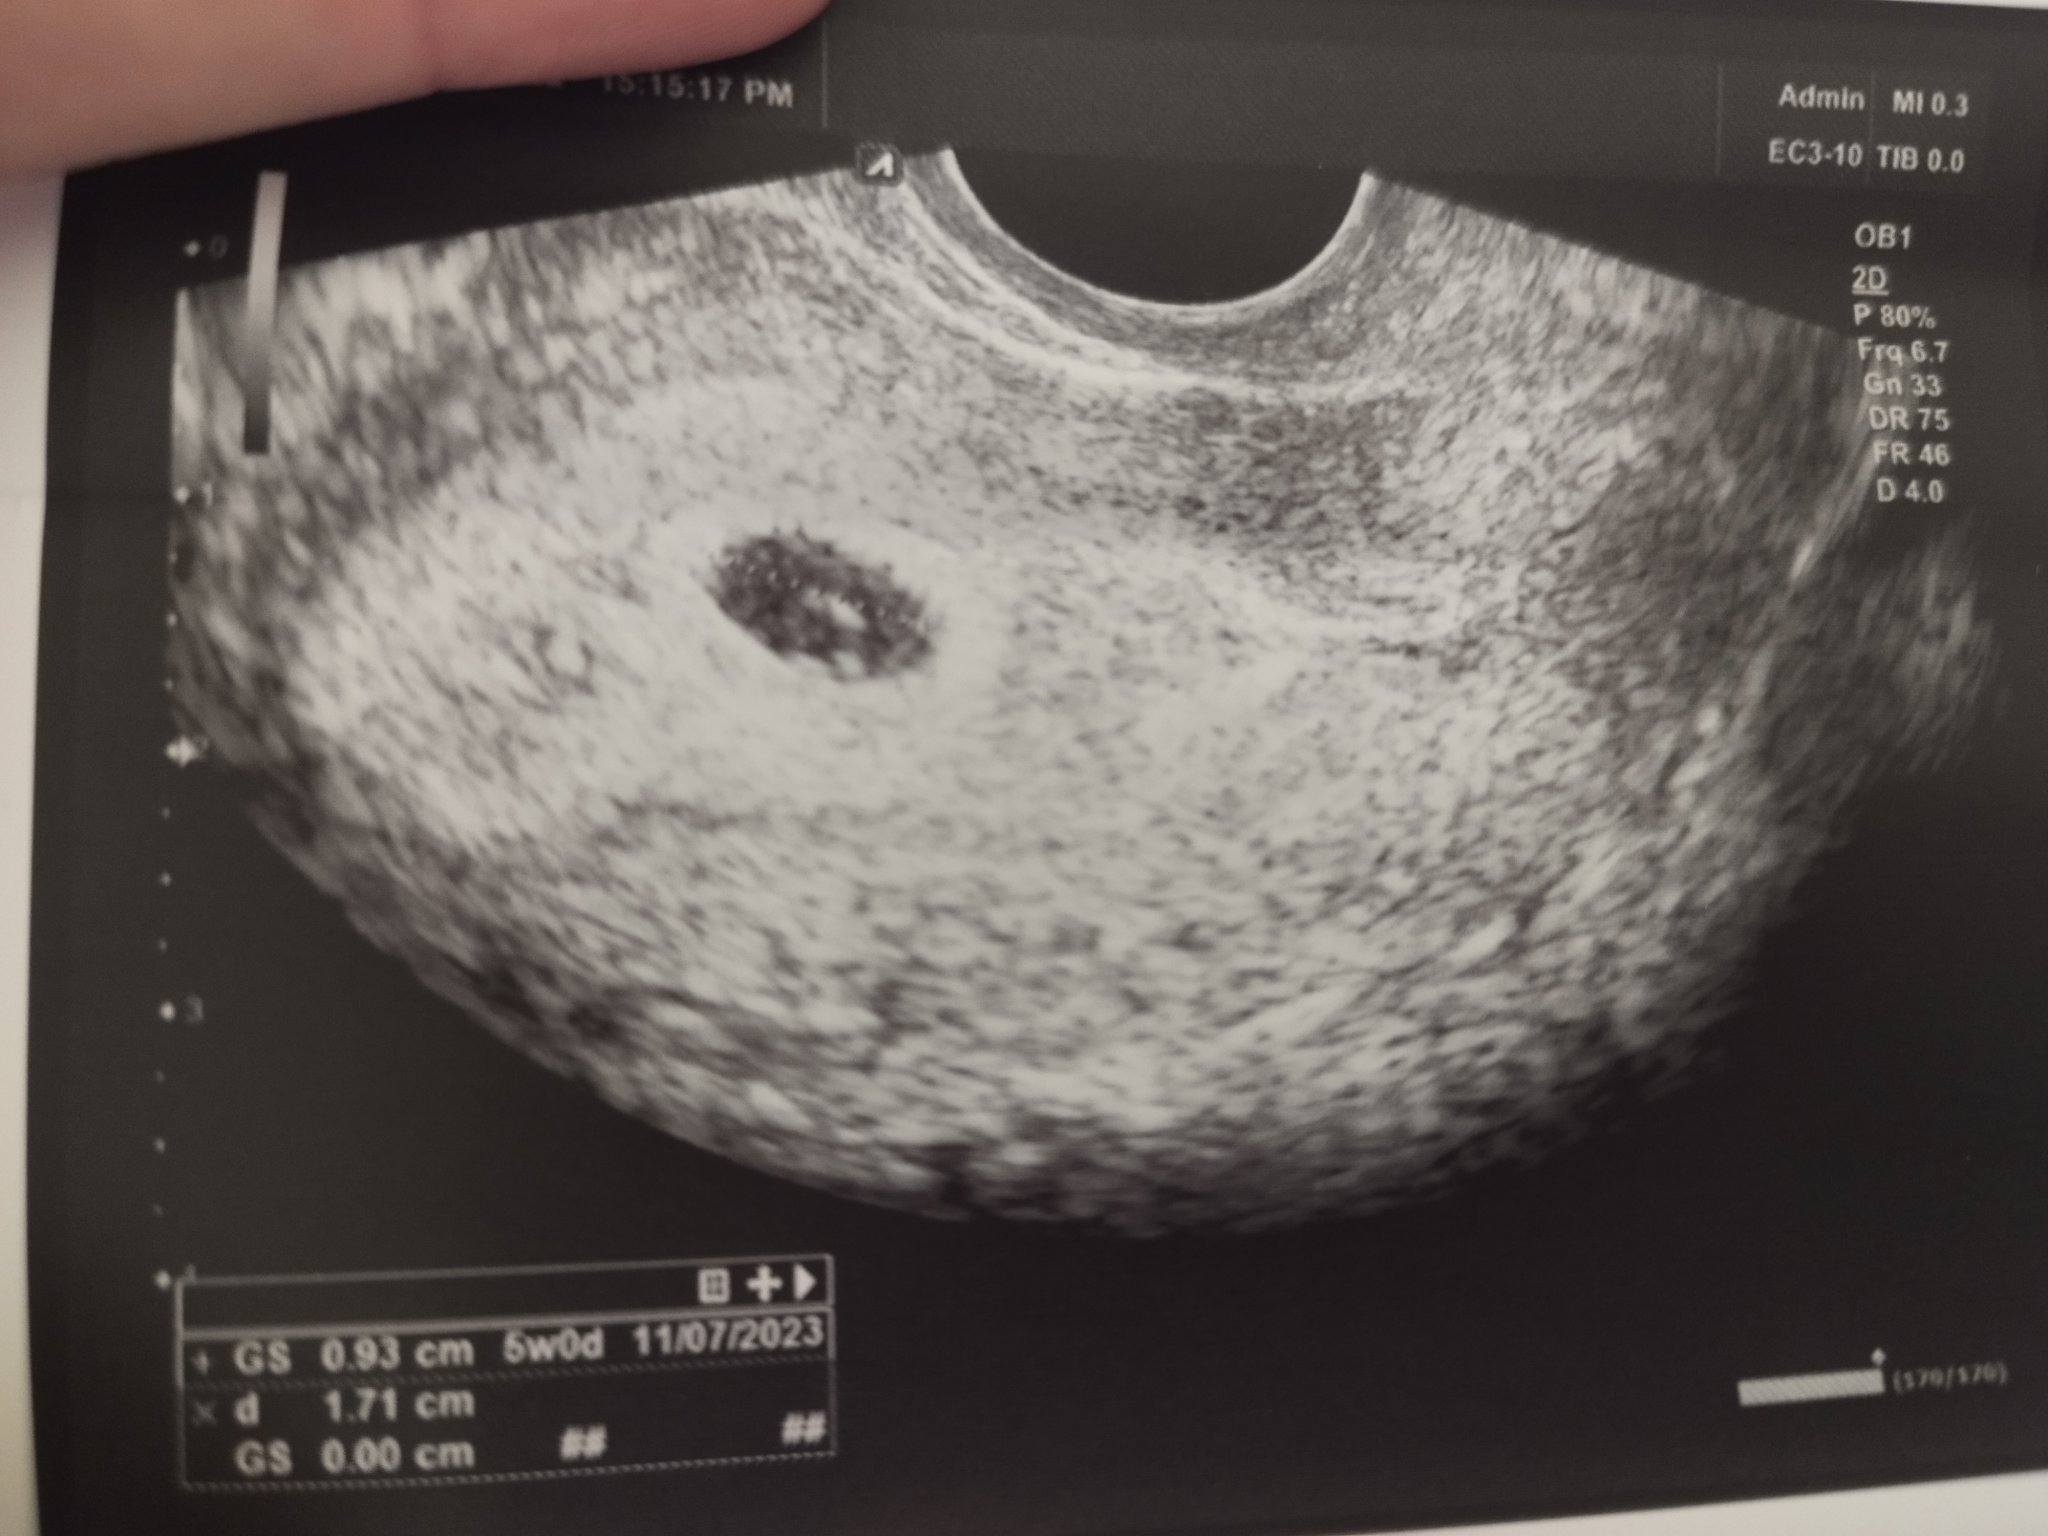

Какво представлява изображението от ехографията на 5-седмична и 2-дневна бременност?

Какво представляват белите точки в плодния сак на ехографската снимка?

Какво представляват черните точки в матката на ехографската снимка?